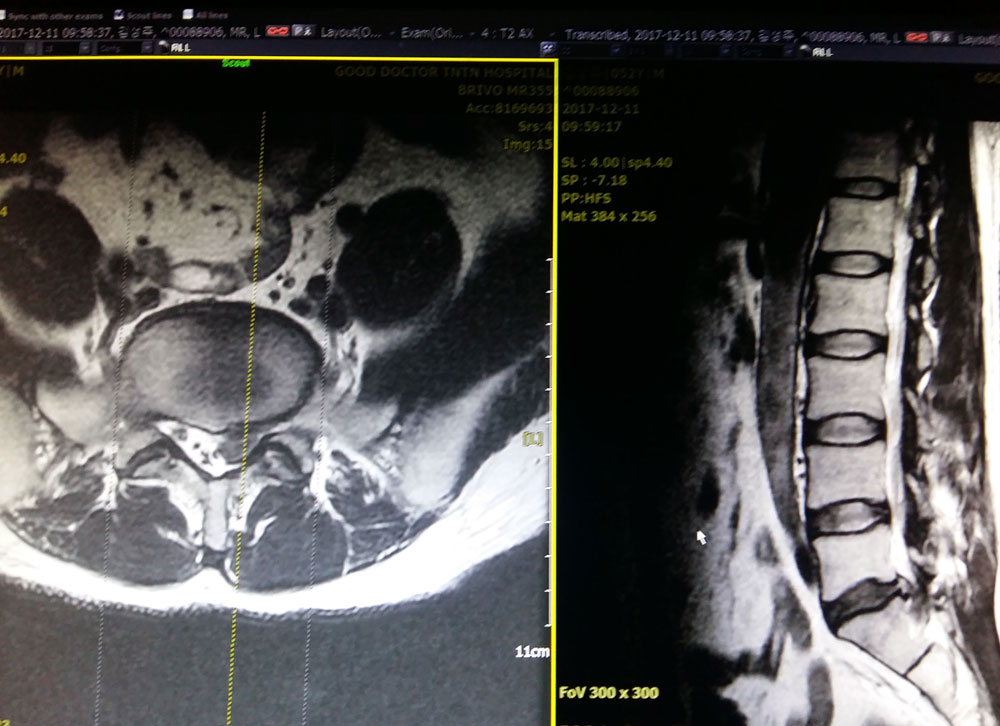

MRI Showing slip disc